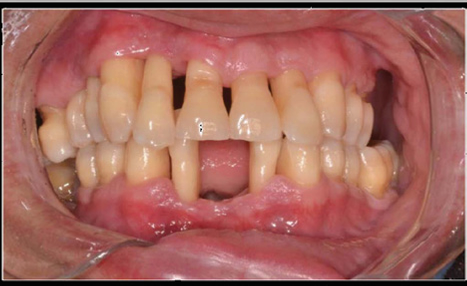

Figure 2 Final photo – Front view.

Extraoral examination was normal. During the intrabuccal examination, presence of several gingival recessions, periodontal clinical parameters were used: visible plaque index [VIP], gingival bleeding index [GBI], probing depth [PD] and clinical insertion oss [CAL]. Gingivitis induced by bacterial plaque and severe AgP was diagnosed. The presence of plaque visible in 41% of the faces and 35% of marginal bleeding justifies the diagnosis of gingivitis, the loss of insertion in all teeth, justifies the diagnosis of periodontitis. The presence of insertion loss between 1 and +10 mm in several teeth with a mean insertion loss of 6.61mm occurring in a period of maximum 20 years and degrees III furcation lesions in all molars in an adult indicates an important pattern of periodontal destruction, not compatible with slow and continuous progression of chronic periodontitis. Another factor that supports the diagnosis of aggressive periodontitis is the rapid progression of insertion loss, due to the presence of vertical bone loss identified in the radiographic examination [for example, teeth 12,11,24,47,42,31,36 and 37] (Figure 4 ).